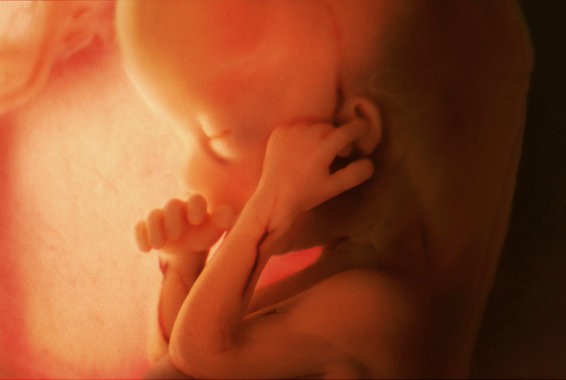

Через восемь недель эмбрион официально считается плодом — этап, на котором он уже имеет человеческие очертания. Плацента постепенно становится полноценной системой жизнеобеспечения.

На 9-й неделе активно формируются нейронные связи. Плод начинает совершать непроизвольные движения: подергивания, сгибания. Частота сердцебиения в этот период может достигать 150 ударов в минуту — позже она снизится, когда контроль возьмёт формирующаяся нервная система.

Второй триместр: быстрый рост и развитие движений

К 14-й неделе плод достигает примерно 14 сантиметров. Укрепляются костные структуры, пальцы рук и ног полностью разделены, формируется мимика и движение глаз. Мозг координирует всё больше процессов, и плод начинает активно исследовать пространство — движениями, реакцией на свет и звуки.